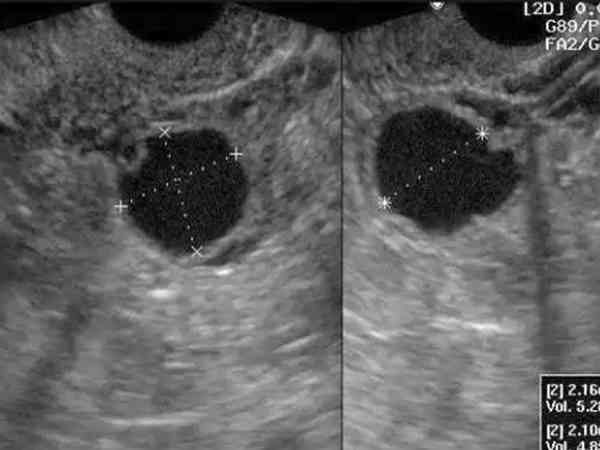

卵泡监测b超检查可以观察到卵巢及卵泡,卵泡张力主要是通过检查卵泡的形态、大小、成熟度来判断卵泡的发育情况,卵泡透声是看卵泡中是否有回声液来判断卵泡质量。一般情况下张力好的都是发育成熟的卵泡,正常卵泡的形状是椭圆形或圆形,大小直径在18-25mm左右,这样就能判断卵泡张力。而透声可以判断卵泡的质量,如果卵泡透声欠佳说明卵泡里有回声液,这会造成卵泡质量下降,有时会影响受孕。卵泡张力和透声一定程度上会影...